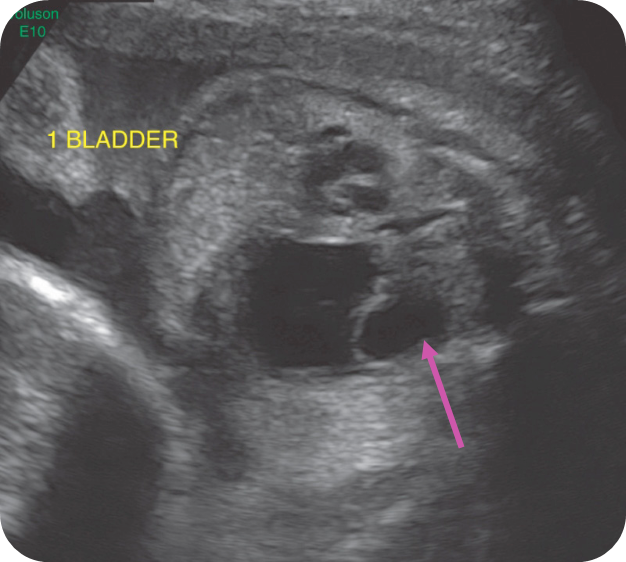

Dilated Bladder